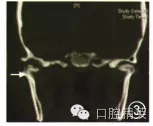

1.病例1:男性,72歲,因左側(cè)外耳道腫脹、流膿3個月并張口受限近1個月就診。口腔科檢查:左側(cè)耳廓皮膚輕度腫脹變厚、暗紅色,外耳道皮膚腫脹明顯、觸痛,其前下壁有一3 mm直徑瘺口,顳下頜骨關(guān)節(jié)區(qū)腫脹、壓痛,有膿性分泌物溢出,張口中度受限,左后牙開殆,顳下頜關(guān)節(jié)三維CT檢查示:左髁突局部有骨質(zhì)缺損,周圍軟組織腫脹模糊(圖1)。既往有糖尿病、高血壓、心臟病病史,空腹血糖12.3 mmol/L,血壓160/100mmHg(1 mmHg=0.133 kPa),C反應(yīng)蛋白偏高,膿液細(xì)菌培養(yǎng)為銅綠假單胞菌,心電圖示心肌缺血。

圖1病例1術(shù)前CT示死骨形成(箭頭)